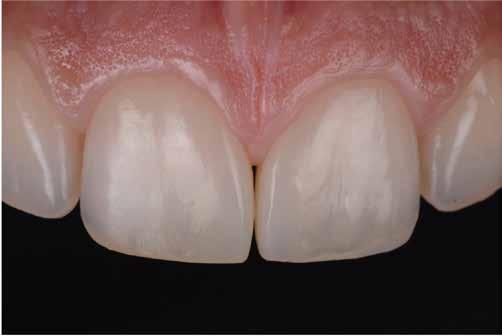

Nem volt kedvencem, de kevésbé kedveltem a hibrid technikát, ahol a palatális fal wax-uppal történő felépítése, majd a nyaki terület szabadkézi megerősítése után a restauráció többi részét mátrixszal lehetett kivitelezni (1. ábra). Bár a kezemben ez valahogy hatékony volt, mégis bonyolult volt.

1. ábra: A wax-up alapú technikák gyakori problémái, a szájpadlásfal apikális része hibás.